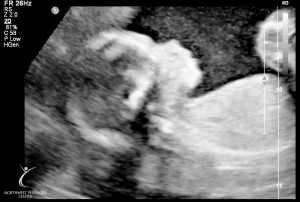

Last Ultrasound